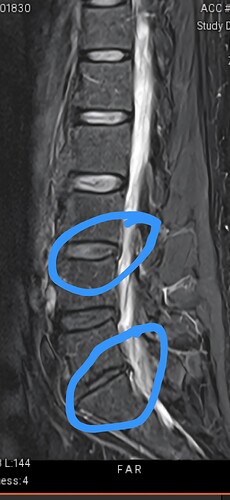

Anyways, finally had my mri on Thursday. I have a follow up with the specialist tomorrow on next steps, although I’m pretty certain that a back fusion is in my near future.